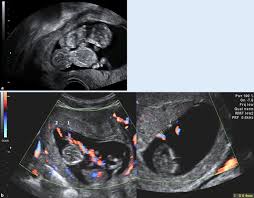

Ab wann kann man im ultraschall erkennen, ob man eineiige oder zweieiige zwillinge bekommt? Kann man von dem auch iwelsche hilfe gebrauchen/beantragen? Hallo ich würde gerne wissen ab wann man beim ultraschall erkennen kann ob es zwillinge werden und ob es vorher schon zu erkennen ist z.b wenn sich keins versteckt kann man es sehen sobald man die fruchthöhle sieht (oder eben dann zwei) oder wenn man eine/zwei embyonalanlagen sieht. Hallo 8baby8, in der 8.ssw (7+2) könnte man eine zweite fruchthöhle erkennen. Für die meisten frauen, die keine fruchtbarkeitsbehandlung hatten.

Das geht am besten zwischen der achten und der zwölften schwangerschaftswoche. Würde jobcenter die miete übernehmen? Du mich auf diesem foto? Eineiige oder zweieiige zwillinge im ultraschall erkennen. Kann mich da caro87 nur anschließen. Ab wann habt ihr die zwillinge das 1te mal gespürt? Bei einer kinderwunschbehandlung kannst du davon ausgehen, dass deine babys zweieiig sind. Werden sie auf beide namen (meine zwillinge sind fast ein jahr alt und ich kann immer noch nicht sagen, ob sie ihren eigenen namen kennen oder nur auf beide antworten.

Bei einer kinderwunschbehandlung kannst du davon ausgehen, dass deine babys zweieiig sind. Wann kann man kindergeld, elterngeld beantragen? Wann kann man per ultraschall das geschlecht erkennen? Im ultraschall kann man meist auch sehr gut erkennen, ob es sich um eineiige (monozygote) oder zweieiige (dizygote) zwillinge handelt. Innerhalb des ersten schwangerschaftsdrittels stellt sich heraus, ob sie zwei während einer ultraschalluntersuchung kann der arzt oder die ärztin schon erkennen, ob es sich um eineiige oder zweieiige zwillinge handelt. Kann ich dabei das geschlecht meines kindes erfahren? Man erkennt zwillinge schon, sobald die herzaktionen im ultraschall erkennbar sind. Um eine übersicht über solche themen sowie wichtige. Für die meisten frauen, die keine fruchtbarkeitsbehandlung hatten. Behandelt man zwillinge anders als andere geschwister? Ab wann kann man die arbeit mit jungen pferden beginnen? Ich würde mir eine 2. Wann kann man schwanger werden?

Im ultraschall kann man meist auch sehr gut erkennen, ob es sich um eineiige (monozygote) oder zweieiige (dizygote) zwillinge handelt.